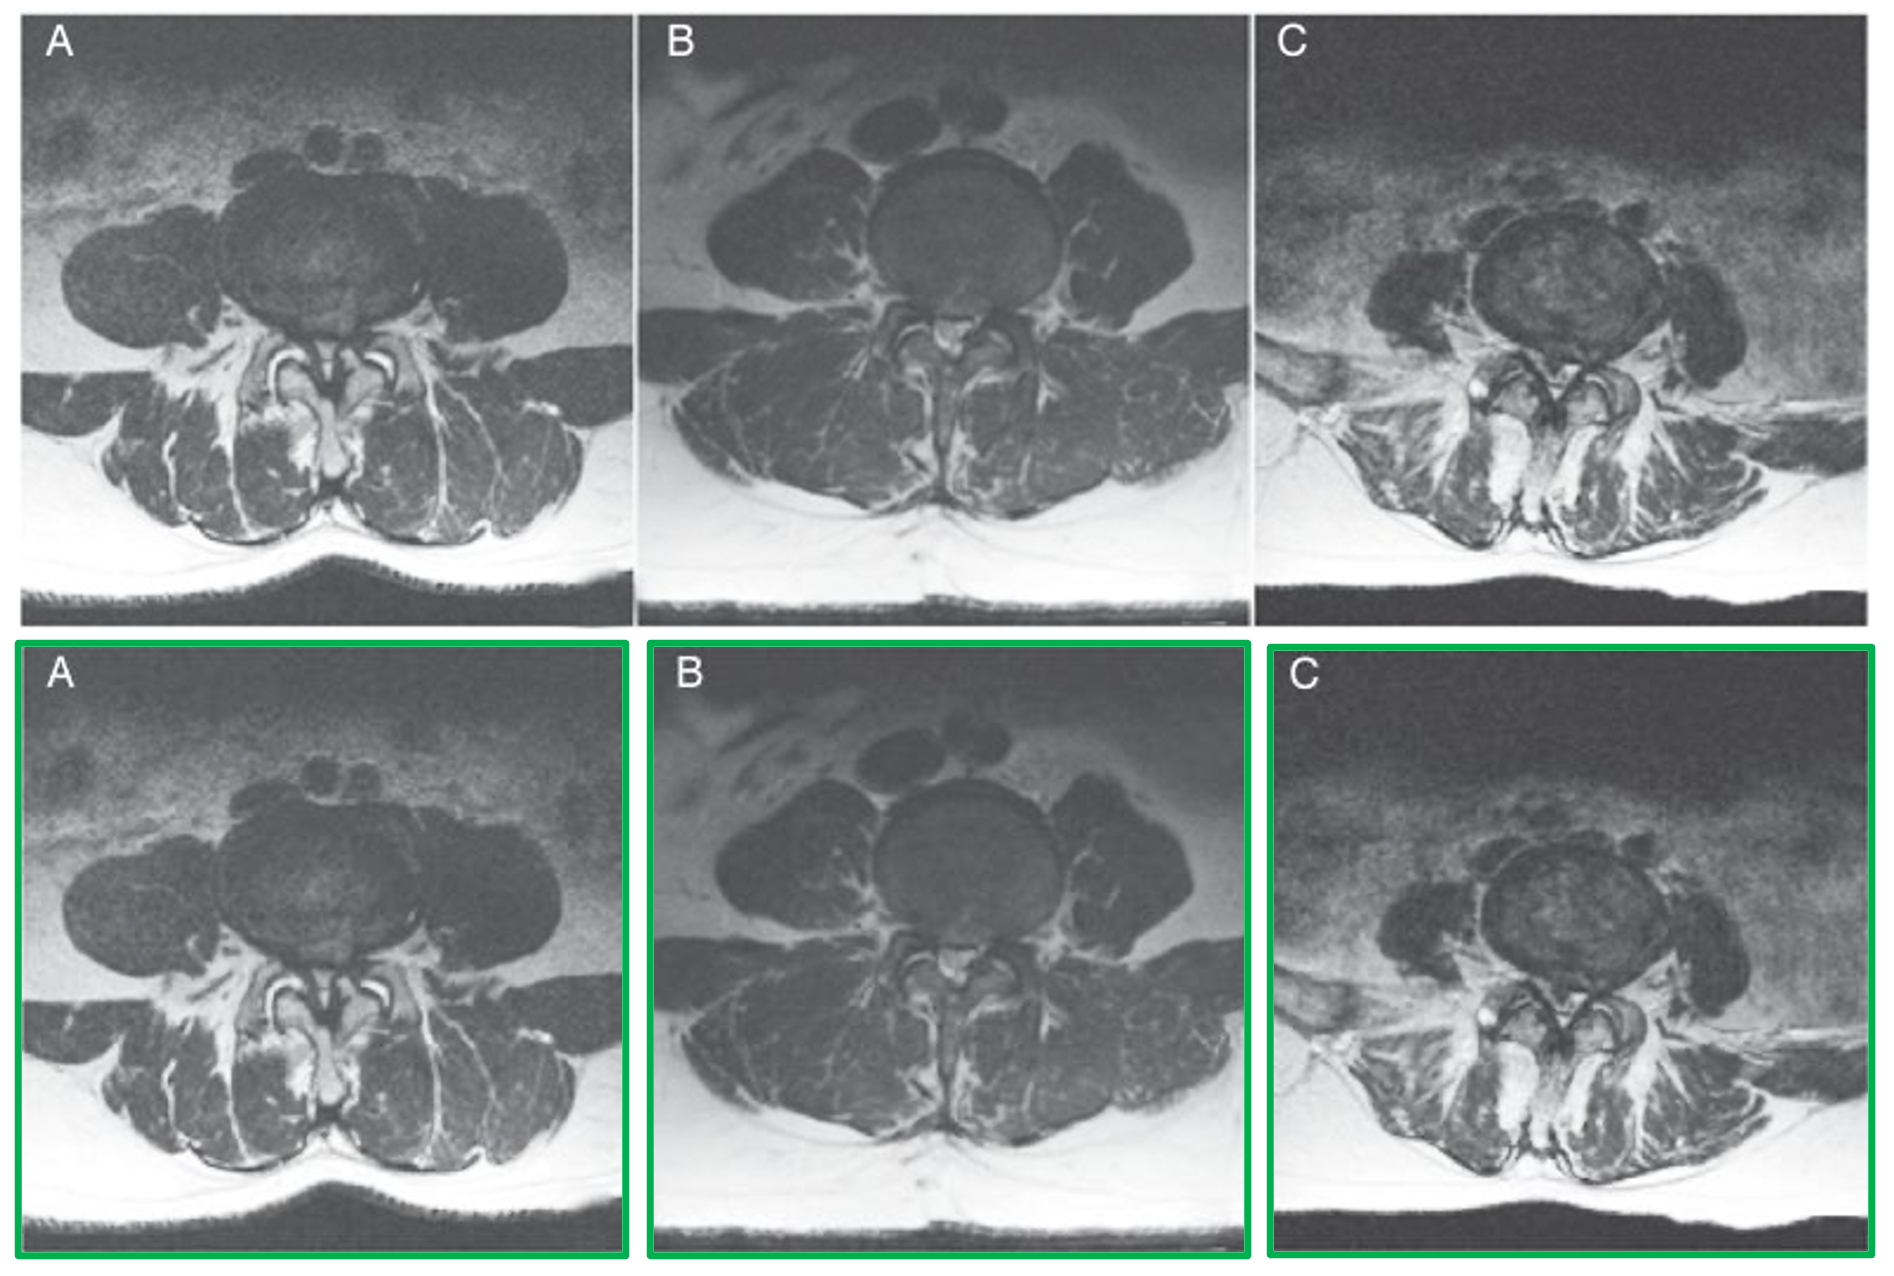

Articles: For scientific documents, we extract the figures as images. However, many of these figures contain multiple sub-figures, which can take nonconventional grid shapes and are labeled irregularly making the task of splitting into sub-figures and pairing with the correct sub-caption non-trivial. Since most compound figure layouts are not uniform and vary in the whitespace in between sub-figures, we train an object detection model based on the YOLO architecture [59] on sub-figure annotation datasets MedICaT and ImageCLEF 2016 [122, 38]. See more details in section 8.3 of the appendix including examples of non-trivial cases.

Articles: The majority of our curated PubMed data uses alphabetic labels in compound figures to denote sub-figures, which increases the complexity of pairing individual sub-figures from compound figures to sub-captions. Our solution leverages an optical character recognition (OCR) 111https://github.com/JaidedAI/EasyOCR on each sub-figure to detect the sub-figure labels, which we then match to the extracted sub-caption labels. To improve the reliability of this approach, we upscale the detected sub-figures by a factor of 4 to enlarge the sub-figure text label for OCR. We also impose a 95% confidence threshold on predicted text to isolate the sub-figure label, as text detected at lower confidence is often non-label text present in the figure (e.g. axis titles, graphs). We then attempt to match the detected sub-figure label with the sub-caption label. If a match is found, we pair the selected sub-figure and sub-caption. Despite the generality of this approach, we identified a few failure cases and proposed an error handling solution for these cases in section 8.5 of the appendix.